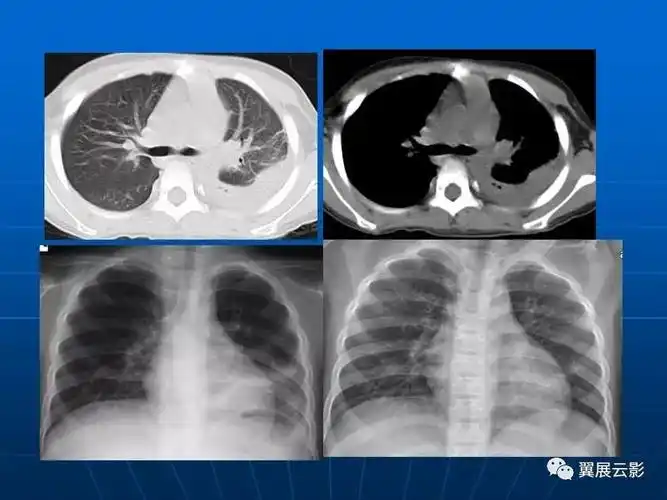

肺部炎症新认识